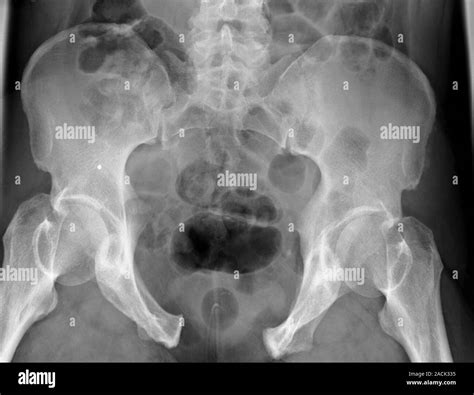

Diagnosing a Broken Pelvis Open Book Fracture

Diagnosing a broken pelvis open book fracture involves a combination of physical examination and imaging tests. The diagnostic process typically includes:

• Physical examination to assess pain, swelling, and deformity.

• X-rays to visualize the pelvic bones and identify the fracture.

• CT scans to provide detailed images of the pelvic structure and assess the extent of the injury.

• MRI scans to evaluate soft tissue damage and internal injuries.

In some cases, additional tests such as angiography may be performed to assess blood flow and identify any internal bleeding.